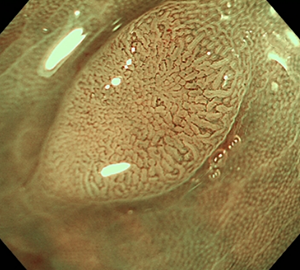

コールドスネアポリペクトミー(CSP)

合併症の非常に少ない優れた治療法であることから、近年大腸ポリープの外来切除法として急速に施行件数が増えてきています。当院ではこのコールドスネアポリペクトミーを主体としたポリープ切除を行っています。

![]() |

|

| 1:ポリープを見つけます。 | 2:狭帯域光画像併用拡大観察で詳細に観察します。 | |

| 3:病変をスネアに通します。 | 4:周囲の正常粘膜をしっかり入れながら、病変を絞扼していき... | |

| 5:切除します。切除検体は吸引回収し病理検査を行います。 | 6:切除後に洗浄・観察して、病変の遺残ががないことを確認します。 |